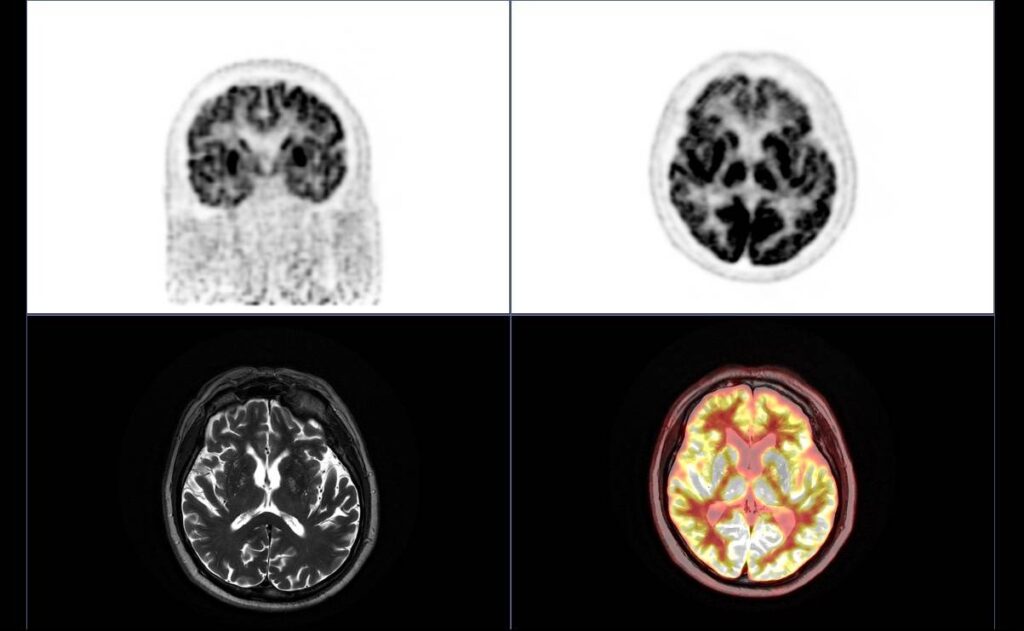

El estudio de la imagen molecular cerebral permite, hoy en día, identificar precozmente las alteraciones morfometabólicas cerebrales que se producen en la enfermedad de Alzheimer, lo que potencialmente podrá resultar una herramienta eficaz para monitorizar la respuesta frente a futuras terapias.

Disponer de equipos de última tecnología como el PET/RM permite identificar y cuantificar en un mapa cerebral los depósitos de sustancia amiloide y determinar el grado de atrofia y patrones de alteración del metabolismo de la glucosa en diferentes áreas del cerebro, variables todas de suma importancia para el estudio del Alzheimer y de otras enfermedades neurodegenerativas.

La técnica híbrida PET/RM permite, de forma sincrónica, fusionar la imagen estructural de la Resonancia Magnética (RM) con la imagen metabólica de la Tomografía por Emisión de Positrones (PET), lo que resulta ideal para el estudio de la enfermedad neurodegenerativa, proporcionando la máxima información en un tiempo récord. “Un abordaje completo que nos permite analizar distintas áreas cerebrales integrando, de forma simultánea, la información que nos proporcionan los biomarcadores de imagen y de metabolismo cerebral con los análisis complementarios de cuantificación mediante inteligencia artificial”, afirma el Dr. Eduard Riera, coordinador de medicina nuclear de Cetir Ascires, basándose en su experiencia con el primer PET/RM de Cataluña, ubicado en el centro médico de Cetir Ascires Viladomat, en Barcelona.